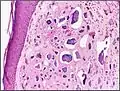

Histopathology of calcinosis cutis in human tissue